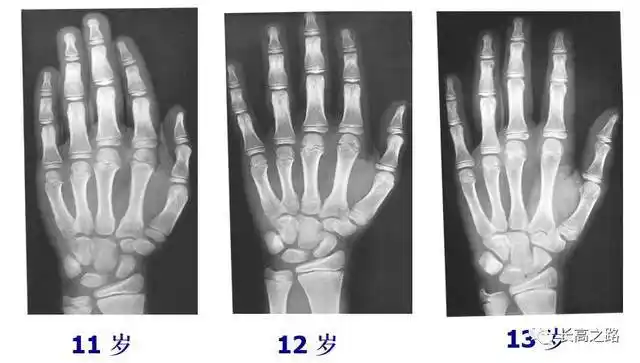

12年男娃骨龄偏大2岁求大数据推给懂友

帮忙看看这个骨龄片,12周岁六个月的男孩子,骨龄片上显示骨龄多少岁?

教你简单识别孩子的骨龄片

中国儿童标准骨龄片